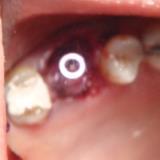

Immediate Implant Placement

A molar either maxillary or mandible always represents a little difficult and tricky scenario for implant placement immediately after extarction. There is always some sacrifice for the location, angle etc. however you save some time and patients go through a procedure once and it is a reliable method of replacing a tooth, when feasible. Dental implant is always a compromised replacement and a tooth restored with immediate placement is not any different.